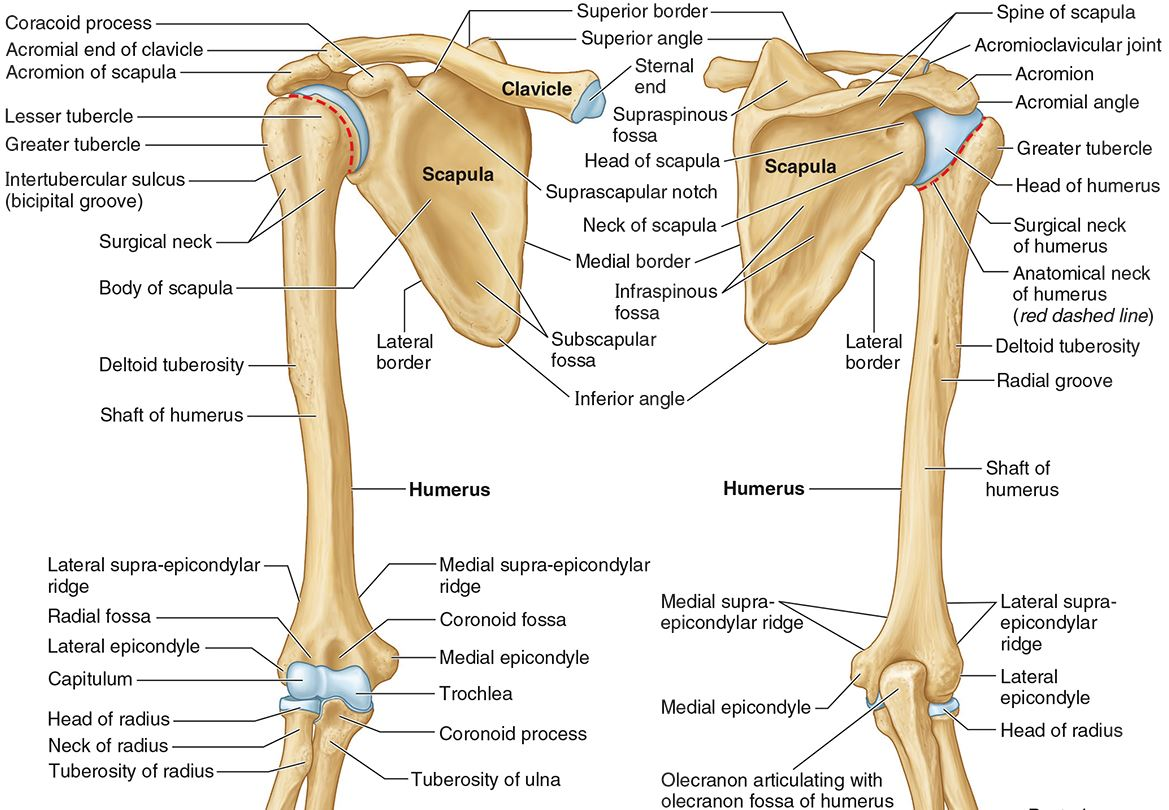

What part of the humerus is this?

The head of the humerus articulates with the scapula at the glenohumeral joint.

What part of the humerus is this?

The anatomic neck is an indentation distal to the head and provides an attachment for the fibrous joint capsule of the glenohumeral joint.

What part of the humerus is this?

The greater tubercle lies lateral and distal to the anatomic neck.

What part of the humerus is this?

The lesser tubercle lies on the anterior/medial side of the humerus, just distal the anatomic neck.

What part of the humerus is this?

The intertubercular (bicipital) groove lies between the greater and lesser tubercles.

What part of the humerus is this?

The surgical neck is a narrow area distal to the tubercles. It is a common site for proximal humerus fractures.

What part of the humerus is this?

The humeral shaft features the deltoid tuberosity laterally for the distal insertion of the deltoid muscle.

What part of the humerus is this?

The radial groove is an oblique depression that contains the radial nerve and deep brachial artery.

Which parts of the humerus is this?

The medial and lateral epicondyles are distal prominences to which many forearm tendons attach, near the elbow joint.

Which parts of the humerus is this?

The medial and lateral supracondylar ridges extend superiorly from the medial and lateral epicondyles.

Which parts of the humerus is this?

The trochlea and the capitulum (the condyles) are the most distal surfaces of the humerus, where it articulates with the forearm bones at the elbow joint

What part of the humerus is this?

The olecranon fossa is a posterior depression above the trochlea that receives that olecranon process of the ulna

What part of the humerus is this?

The coronoid fossa is an anterior depression above the trochlea that receives that coronoid process of the ulna.